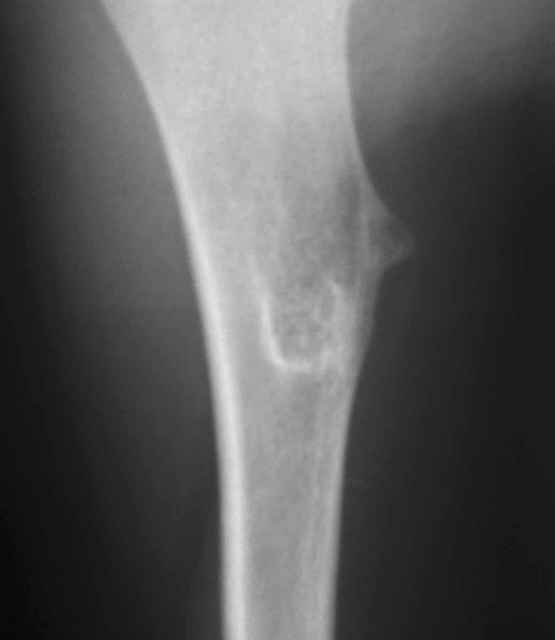

Уважаемый Антон. У ребенка типичный костно-хрящевой экзостоз в области проксимальной трети плечевой кости. Удаление экзостоза, уровень резекции по проекции интактной кортикальной пластинки. Костная пластика не требуется

Согласен с Ihor и Игорем Владимировичем - имеет место костно-хрящевой экзостоз. Необходима резекция в пределах здоровой кости без костной пластики

Обычная Solitary Osteochondroma или экзостоз относится к часто встречающимся доброкачественним опухолям. При давлении на нерв или на сосуды могут быть характерные симптомы, а так клинически не проявляется и обнаруживается случайно при исследованиях по другим поводам.

Обычная простая плоскостная резекция решит все